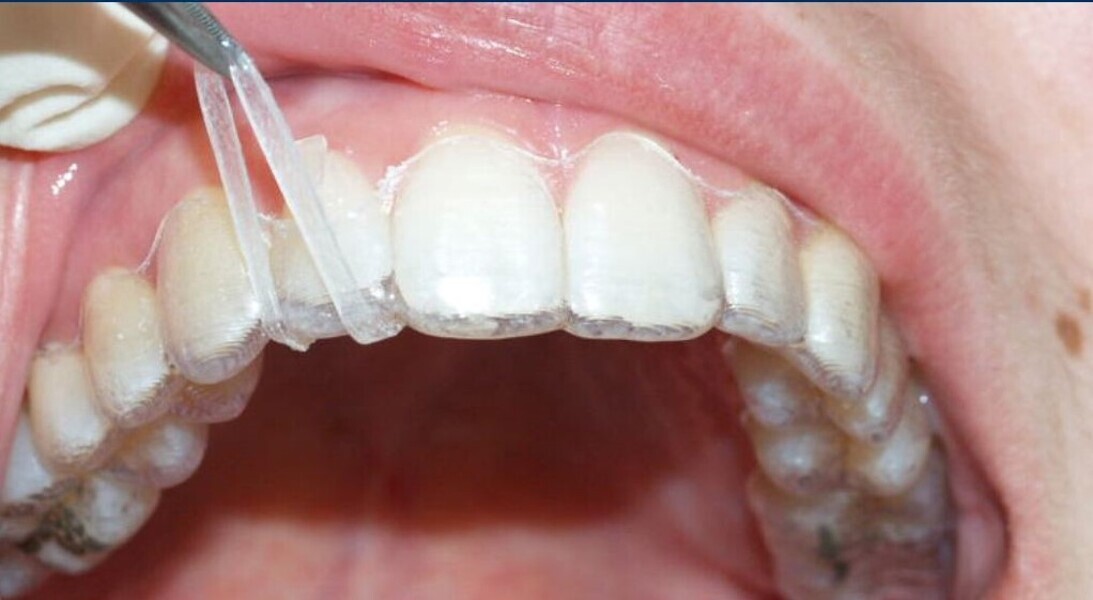

Fig. 19a: After six months of the Carriere Motion appliance and aligners. (a) Lateral view. (b) Occlusal view.

Fig. 19b: After six months of the Carriere Motion appliance and aligners. (a) Lateral view. (b) Occlusal view.